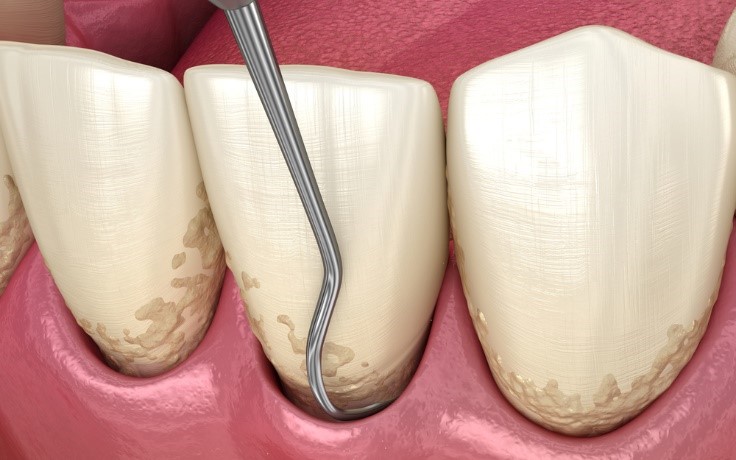

Nạo túi nha chu là thủ thuật nha khoa giúp làm sạch sâu bên trong túi nha chu, khoảng trống giữa nướu và chân răng do viêm nha chu gây ra. Phương pháp này loại bỏ mảng bám, vi khuẩn và mô viêm, giúp ngăn ngừa mất răng và hỗ trợ nướu phục hồi.

Bác sĩ dùng dụng cụ chuyên dụng để loại bỏ mảng bám, vôi răng, vi khuẩn và mô viêm bên trong túi nha chu. Trong một số trường hợp nặng, có thể cần bóc tách nướu để làm sạch sâu hơn.